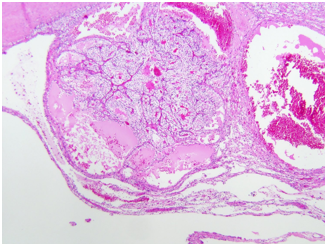

Đại thể

Thường là khối u vỏ thận một bên và đơn ổ, kích thước trung bình khoảng 7 cm. Khối u thường có ranh giới rõ, được bao quanh bởi giả bao u, phát triển theo kiểu đẩy nở và lồi ra từ vỏ thận. Hình thái đại thể đa dạng với thành phần đặc và nang, kèm các vùng xơ hóa màu xám và các ổ xuất huyết mới hoặc cũ màu nâu; hoại tử và biến đổi nang gặp thường xuyên. Khối u có màu vàng ánh kim do hàm lượng lipid cao; các khối u có độ mô học cao hơn có thể không có màu vàng do hàm lượng lipid và glycogen thấp hơn. Các vùng mềm, dạng thịt có thể phản ánh sự hiện diện của biệt hóa dạng sarcomatoid. Thường xuyên ghi nhận xâm lấn tĩnh mạch thận và xoang thận. Tổn thương hai bên và đa ổ là đặc điểm gợi ý bệnh lý di truyền.

Về phân giai đoạn, các khối u có kích thước lớn hơn 7 cm hầu như luôn xâm lấn mỡ xoang thận; nếu không quan sát thấy xâm lấn ở các khối u lớn, cần tiến hành xem xét lại đại thể bổ sung. Xâm lấn bao thận được đặc trưng bởi sự tiến triển không đều và gián đoạn của khối u vào mô mỡ quanh thận kèm theo mất đường viền ngoài lồi đều, nhẵn của thận; khối u lồi đều, nhẵn và được bao phủ bởi giả bao ung thư không được xem là xâm lấn mỡ quanh thận. Để chẩn đoán xâm lấn, tế bào u phải tiếp xúc trực tiếp với mô mỡ hoặc xâm nhập dạng các lưỡi không đều vào mô quanh thận, có hoặc không kèm phản ứng xơ sinh. Xâm lấn xoang thận là con đường lan tràn ngoài thận thường gặp nhất và thường xảy ra trước xâm lấn bao thận; khác với bao thận,xoang thận không được ngăn cách với nhu mô thận bằng một bao xơ riêng biệt. Không được coi là xâm lấn thực sự nếu khối u vẫn được ngăn cách với các cấu trúc xoang bởi một viền nhu mô thận; được coi là xâm lấn xoang thận khi khối u lồi rõ vào mô mỡ xoang thận vượt quá nhu mô thận, kể cả khi vẫn được bao phủ bởi mô liên kết thưa. Việc khối u bao quanh các cấu trúc mạch máu hoặc bạch mạch lớn là dấu hiệu gợi ý xâm lấn mỡ xoang thận. Xâm lấn mạch máu có thể biểu hiện dưới dạng các nốt u trong xoang thận; trong trường hợp lòng mạch bị bít một phần, sự hiện diện của một lớp nội mô đơn độc phủ lên bề mặt khối u không loại trừ xâm lấn mạch máu. Xâm lấn tĩnh mạch nhỏ thường hàm ý xâm lấn tĩnh mạch lớn, và xâm lấn xoang thận thường đồng nghĩa với xâm lấn tĩnh mạch thận, do đó cần được thăm khám và đánh giá một cách thận trọng.

Hình 2. ccRCC đã xâm lấn mạc Gerotta (pT4)